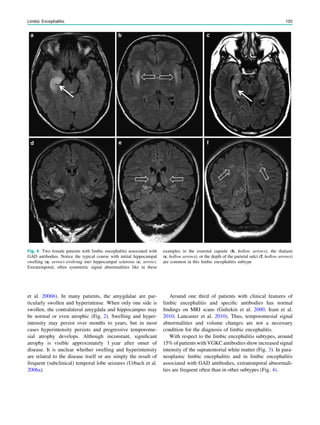

This chapter provides Epilepsy-dedicated MRI protocols

and useful informations regarding angulation, spatial

resolution, and contrast to noise ratios.

1 Introduction

Patients with focal (partial) epilepsies in which an epilep-

togenic lesion has not been found (yet) should be studied